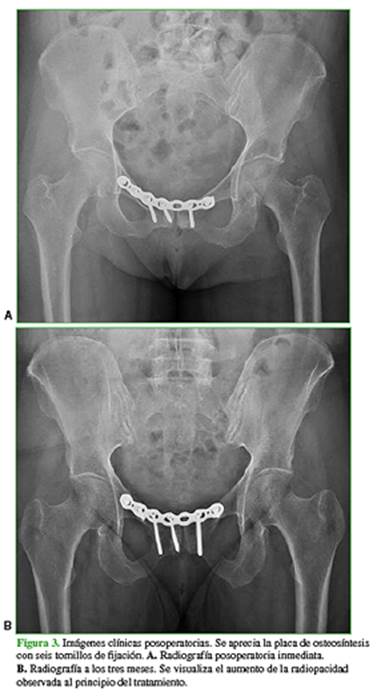

Luego de discutir el diagnóstico y las opciones terapéuticas con la paciente, se decidió realizar una osteosíntesis de la sínfisis del pubis con una placa de reconstrucción de huesos planos de acero inoxidable de 3,5 mm (Stryker® Trauma) y seis tornillos corticales autorroscantes de 3,5 mm (Figura 3). Se logró una fijación estable y no hubo complicaciones técnicas para su aplicación. La paciente comenzó con terapia de rehabilitación a los 15 días de la cirugía, y evolucionó favorablemente, con mejoría progresiva del dolor hasta la remisión completa a las 12 semanas de la operación. A los tres meses, comenzó con gimnasia y, a los seis meses, retornó a la actividad deportiva, sin síntomas.

En nuestro caso, la paciente posmenopáusica con un índice de masa corporal de 21, osteoporosis diagnosticada por densitometría ósea y tratada junto con el Servicio de Reumatología, y el antecedente de tabaquismo constituyeron los factores de riesgo más relevantes para decidir entre los especialistas del equipo médico y la paciente un manejo quirúrgico teniendo en cuenta que, luego de seis meses, el tratamiento primario no resultó adecuado y la paciente deseaba recuperarse rápidamente para continuar con sus actividades diarias y deportivas. El seguimiento radiográfico mostró una buena evolución y el dolor en la región inguinal desapareció a los tres meses de la cirugía; la paciente reanudó su actividad deportiva a los seis meses.